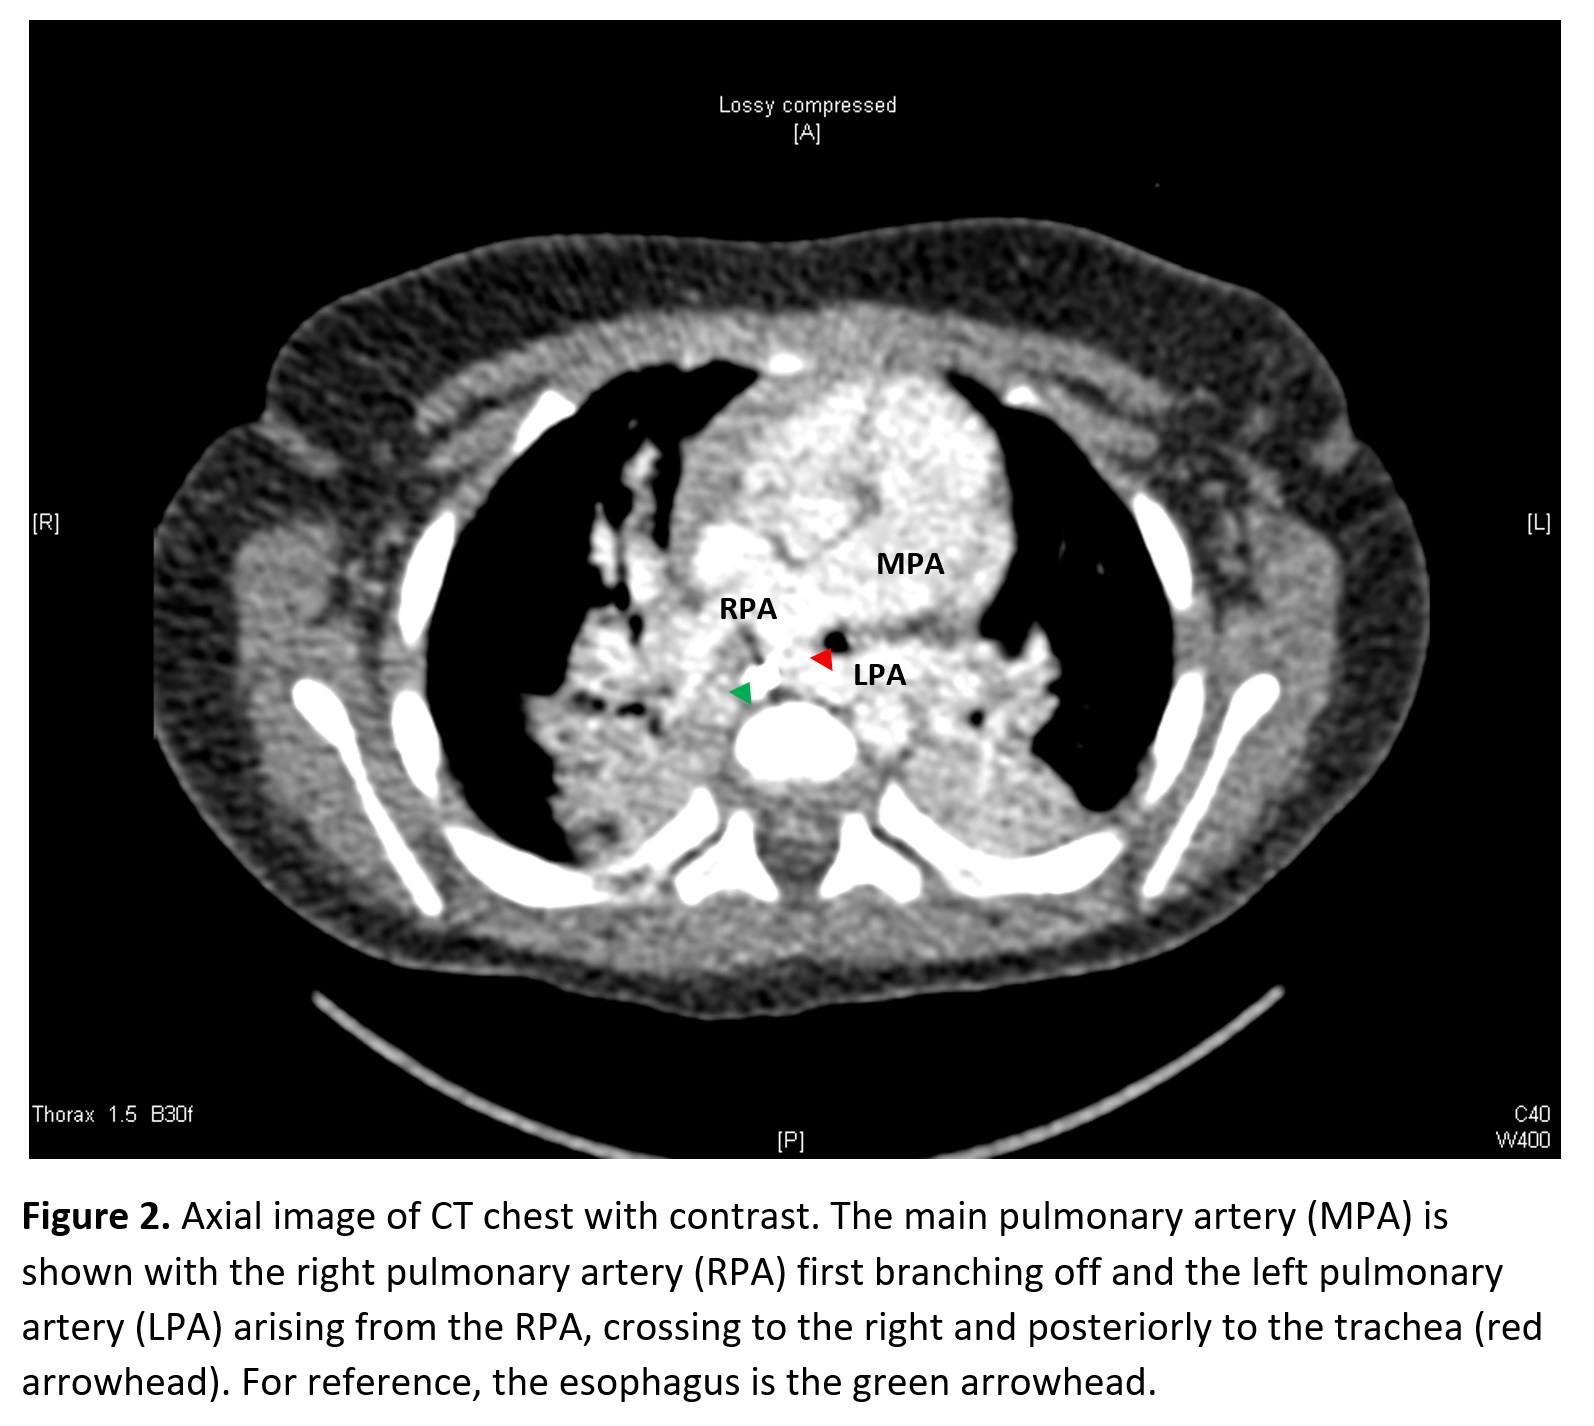

Case Presentation: A 7-month-old former term female with congenital hypothyroidism was admitted for the third time with a diagnosis of bronchiolitis. Her first admission at 7 weeks of age involved an ICU stay requiring intubation and chest tube placement after a chest X-ray showed a right tension pneumothorax. She suffered no other major complications and was discharged home with supportive care within one week. She presented at 5 months of age with respiratory distress, but had a short hospital stay, and was again discharged with supportive care. On her third admission, she presented with increased work of breathing, but over the course of five days there was no improvement on Vapotherm at 8 L/min, until she was transferred to the ICU and intubated. Pulmonary team was consulted and an echocardiogram (ECHO) was obtained and was normal, however the left pulmonary artery (LPA) was poorly visualized. Bronchoscopy revealed a blind pouch of the right mainstem bronchus and severe bronchomalacia. A chest CT with contrast showed an LPA sling causing moderate narrowing of the distal trachea and proximal right mainstem bronchus. Cardiovascular Surgery then performed LPA sling repair. She tolerated the procedure well; however, she developed a fever post-op. Respiratory culture was positive for Moraxella and a 7-day course of Unasyn was given. She was discharged home on post-op day nine at which point she was tolerating oral feeds and stable on room air.

Discussion: An LPA sling is a rare congenital anomaly in which the LPA arises from the right pulmonary artery and tracks between the trachea and the esophagus to the left lung. Most children present in the first year of life with respiratory symptoms including wheezing, stridor, and recurrent lower respiratory tract infections. An ECHO usually establishes the diagnosis and is also helpful as up to 85% of patients have additional cardiac anomalies. Bronchoscopy can identify tracheal stenosis as this requires surgical repair but is less useful as it does not show the anatomy needed for surgical correction. In contrast, cardiovascular CT angiograms aid in surgical planning. Corrective surgery is the mainstay of treatment for symptomatic patients as without surgery, mortality rate can be as high as 90%. Prognosis is excellent but depends on whether tracheal repair is also required.